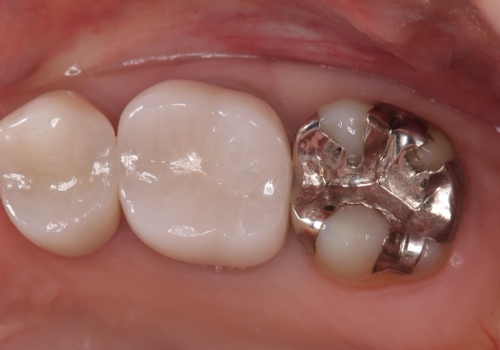

保険のメタルインレーは腐食しやすかったり、適合があまり良くなかったりで二次的にう蝕がインレー下で広がってしまうことが多々あります。

メタルインレーを除去したところ、残存歯質量が少なく破折のリスクを説明し、ゴールドクラウンでのやり替えとなりました。